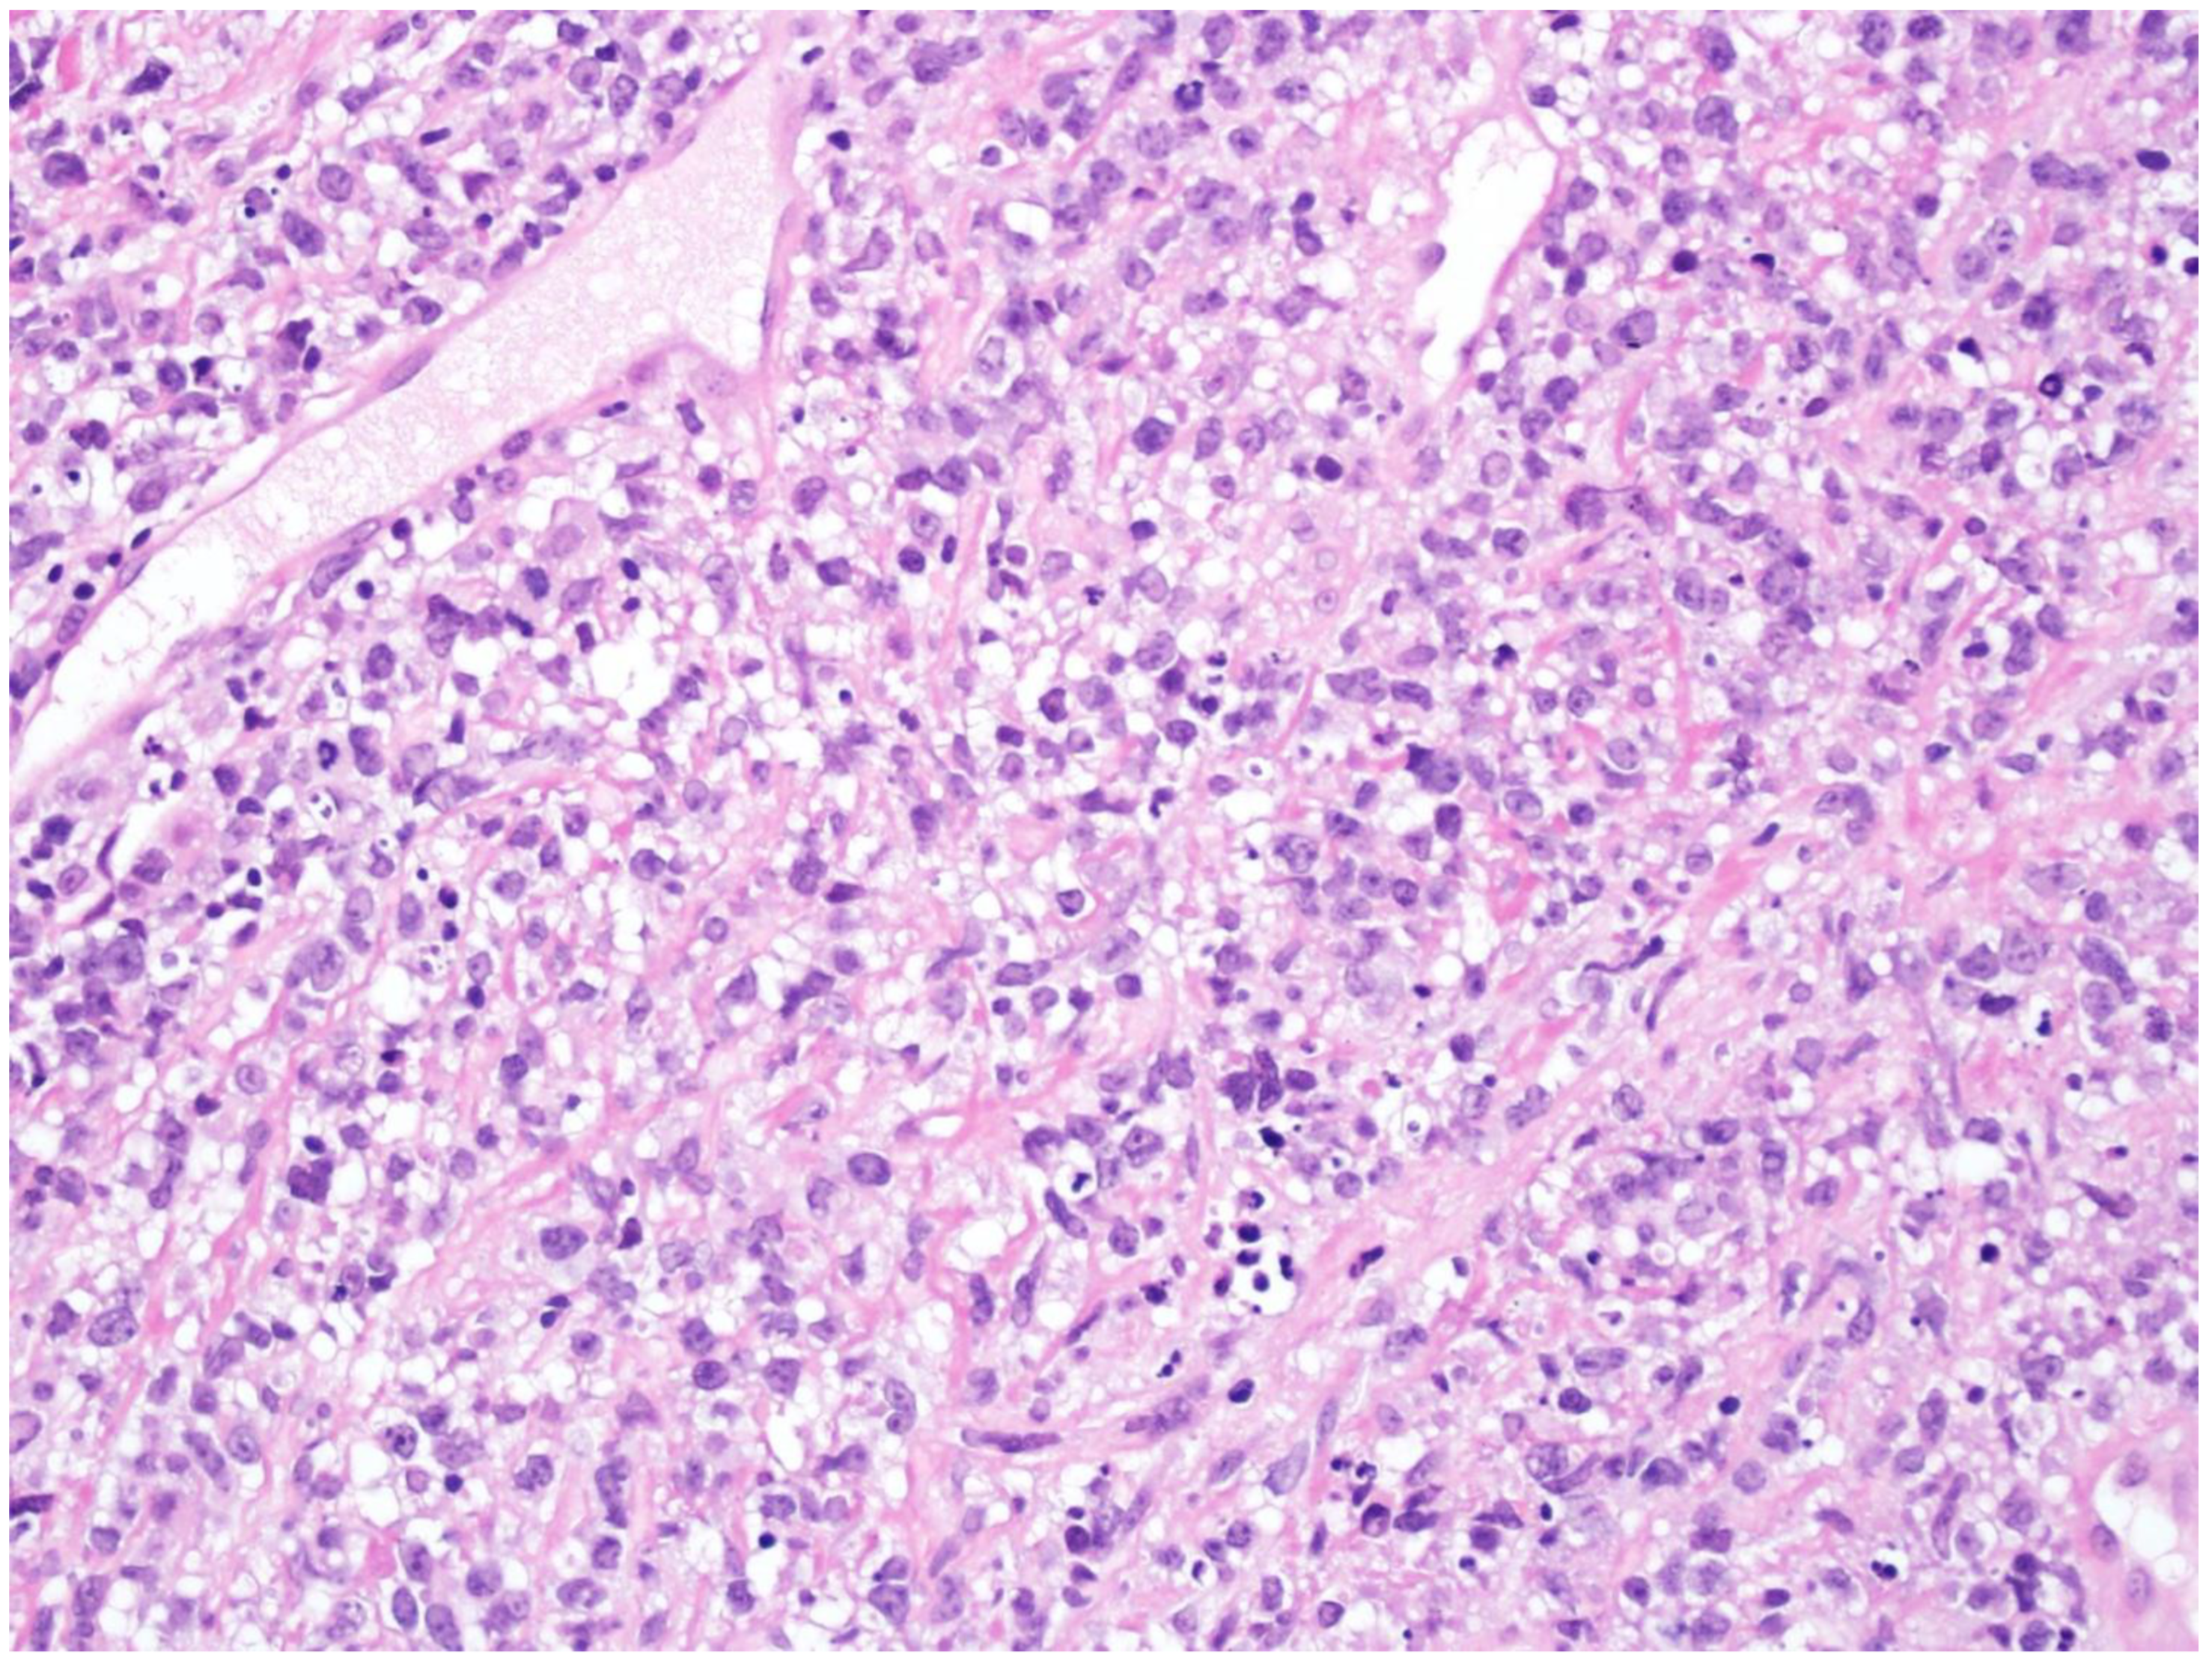

4. T-Cell/Histiocyte-Rich Large B-Cell Lymphoma

| T-cell/histiocyte-rich large B-cell lymphoma |